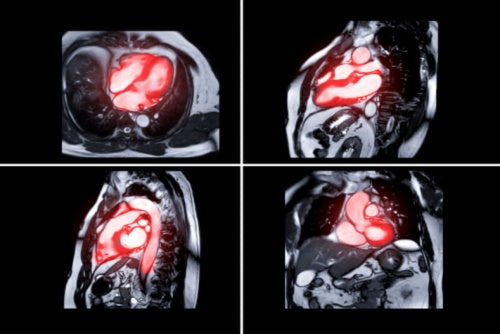

Cardiac magnetic resonance imaging (cardiac MRI)

What it is and how it works: A cardiac MRI is an investigation used to take high-resolution images of the heart using a powerful magnet. Unlike a chest x-ray or CT scan, an MRI does not use x-rays. However, it is very important to remove any metal objects before having the test. During a cardiac MRI, you will be asked to lie down on a table before being moved inside of the machine. It can get quite noisy during the test, however you will be provided with headphones or given the option to listen to some music. You may be asked to hold your breath for some images too. It is also important to remain as still as possible to prevent the final images from being blurred. Although scan times may vary, a cardiac MRI may last from about 30 minutes to over an hour.

What it detects: A cardiac MRI can be requested to help diagnose a range of heart problems, such as coronary heart disease, inherited heart conditions like hypertrophic or dilated cardiomyopathy, and valvular heart disease.